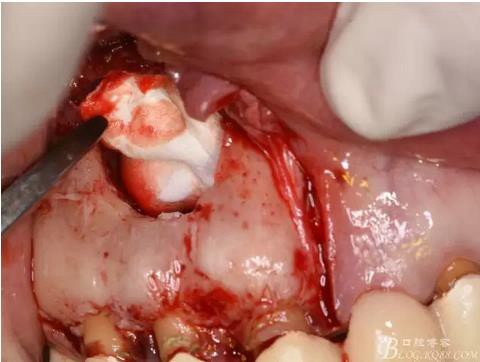

圖13.根尖倒預(yù)備

圖14.吸潮紙尖干燥根管

圖15.取愛如特生物陶瓷材料

圖16.放置在干燥好的根管內(nèi)

圖17.根尖倒充填完畢